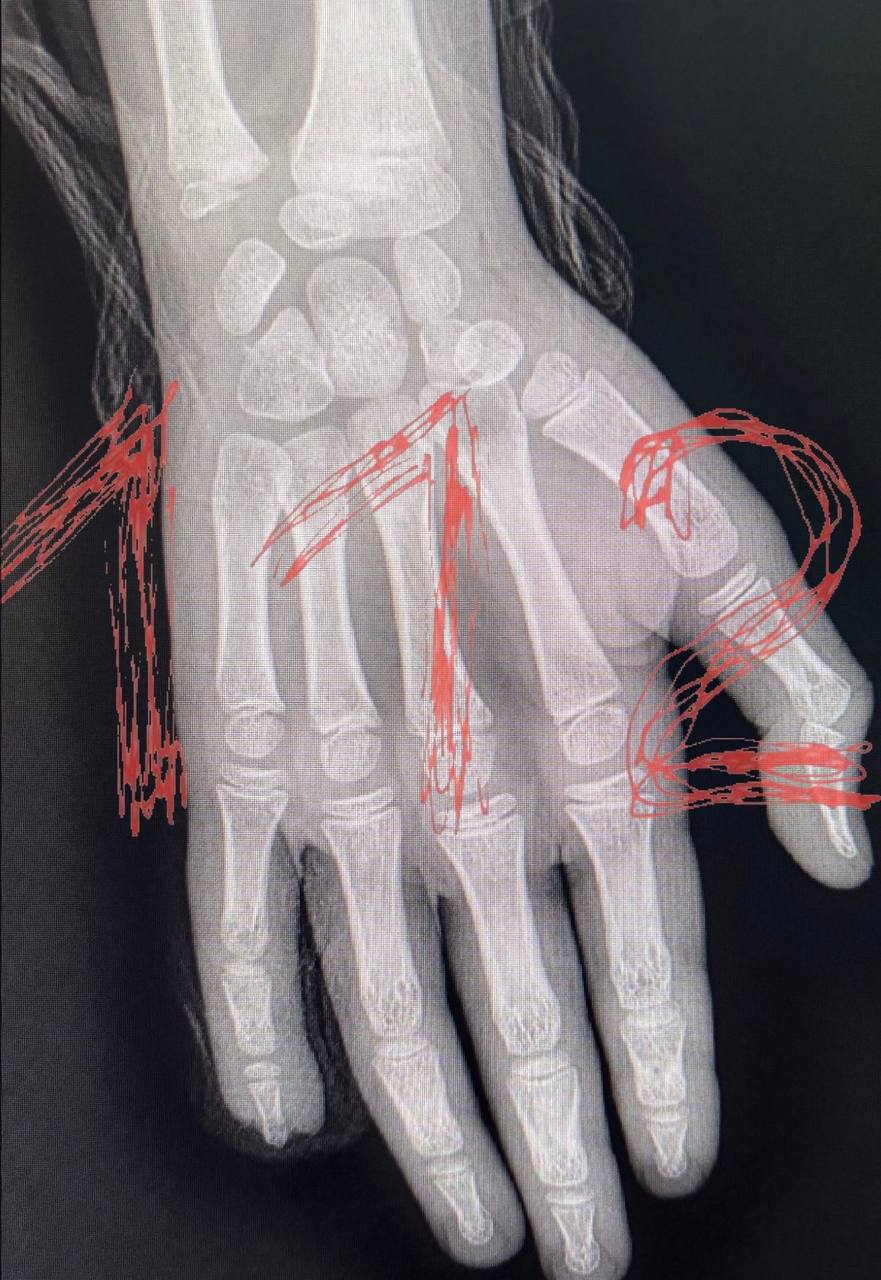

Сотрудники детского сада, по утверждению матери, не вызвали скорую помощь, ограничившись сменой повязки. Родителям сообщили, что без их присутствия вызвать медиков нельзя. Девочку доставили в больницу, где ей наложили швы, однако травма оказалась серьезнее, чем предполагалось. Сейчас ребенку грозит ампутация пальца из-за повреждения кости.

Руководство детского сада до сих пор не связалось с семьей пострадавшей. Родители продолжают обращаться в различные медицинские учреждения в поисках помощи. Ситуация вызвала широкий общественный резонанс и требует тщательного разбирательства.